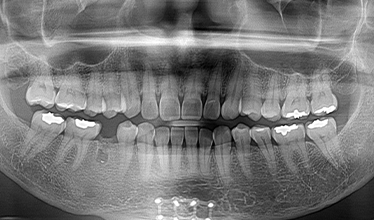

CASE 02

• 치료 전

• 발치 후

• 임플란트 즉시 식립 후